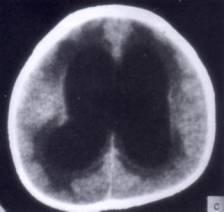

病历摘要:??患者女性,10岁。结核性脑膜炎愈后8月,头痛伴恶心呕吐1周,并渐加重。体检:神清,精神差,反应迟钝,双眼底视神经乳头水肿,双眼外展差,余未见...

问题 病历摘要:??患者女性,10岁。结核性脑膜炎愈后8月,头痛伴恶心呕吐1周,并渐加重。体检:神清,精神差,反应迟钝,双眼底视神经乳头水肿,双眼外展差,余未见明显异常。 下列关于脑脊液的叙述哪些是正确的?

选项 A.脑脊液主要有脉络丛产生 B.脉络丛仅存在于侧脑室中 C.脑脊液主要有蛛网膜颗粒吸收入下矢状窦 D.成人脑脊液的总量约为100~150ml E.正常脑脊液细胞数为0~20×10/L F.颅内静脉窦血栓形成可导致脑脊液吸收障碍 G.脑室内的脑脊液经第4脑室的正中孔和侧孔流入蛛网膜下腔